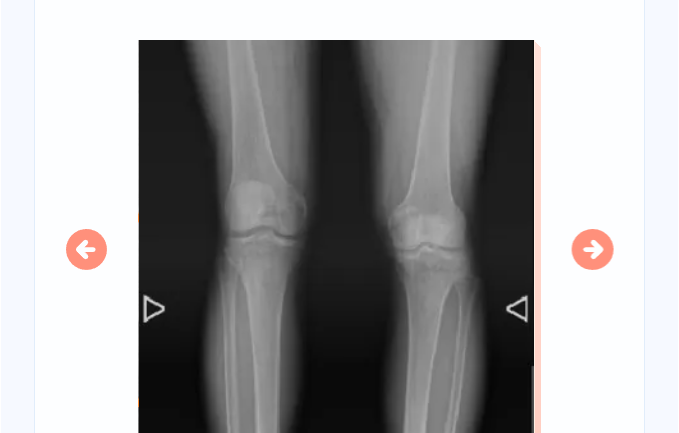

图中可明显看到患者右侧髋臼骨质增生严重